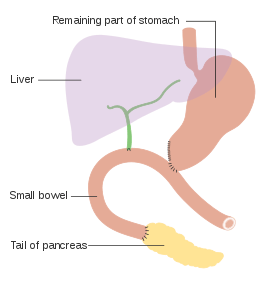

For cancers involving the head of the pancreas, the Whipple procedure is the most commonly attempted curative surgical treatment. This is a major operation which involves removing the pancreatic head and the curve of the duodenum together ("pancreato-duodenectomy"), making a bypass for food from the stomach to the jejunum ("gastro-jejunostomy") and attaching a loop of jejunum to the cystic duct to drain bile ("cholecysto-jejunostomy"). It can be performed only if the person is likely to survive major surgery and if the cancer is localized without invading local structures or metastasizing. It can therefore be performed only in a minority of cases. Cancers of the tail of the pancreas can be resected using a procedure known as a distal pancreatectomy, which often also entails removal of the spleen.[4][6] Nowadays, this can often be done using minimally invasive surgery.[4][6]